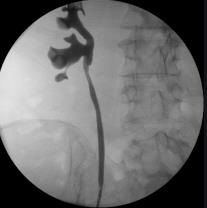

Pielografía retrógrada

Es una técnica radiográfica que permite demarcar, contrastar el uréter y el sistema colector renal (pelvis, infundíbulo y cálices) mediante la inyección de contraste radio opaco bajo presión en el uréter (8).

Indicaciones

La primera indicación para realizar una pielografía retrógrada es visualizar radiológicamente el uréter o el sistema colector dentro del trabajo endourológico habitual. La mejor definición de sistema colector muchas veces es requerida para evaluar defectos de llene del uréter o aparato caliciliar en contexto de estudio de hematuria(9).

- Evaluación obstrucción ureteral congénita.

- Evaluación obstrucción ureteral adquirida.

- Definición de imágenes lacunares y malformaciones de los uréteres o sistemas colectores intrarenales.

- Opacificación y distensión del sistema colector para guiar abordaje percutáneo.

- Evaluación de hematuria.

- Evaluación de lesión del uréter o sistema colector.

Técnica

Se trata de un procedimiento cistoscópico, que puede realizarse bajo anestesia local, requiriendo la misma preparación que una cistoscopía.

Paciente en posición litotomía, acceso endoscópico a vía urinaria inferior. Identificación de orificios ureterales. Una vez identificado el orificio a cateterizar, se debe utilizar algún tipo de catéter ureteral, sea de punta cónica, espiral o de oliva para la inyección directa de contraste en uréter. Se utilizan generalmente catéteres de 4 a 6 Fr.

Previo a la inyección de contraste se toma una placa simple y una vez asegurado la suave cateterización ureteral, no forzar para no dañar la submucosa y evitar una eventual perforación, se procede a la inyección de contraste. Debemos tener presente que la distancia entre el orificio ureteral y la pelvis renal varía entre 20 a 25 cm, por ello cualquier tipo de catéter que se utilice está demarcado. Se suele utilizar 10 ml de solución de contraste al 50%.